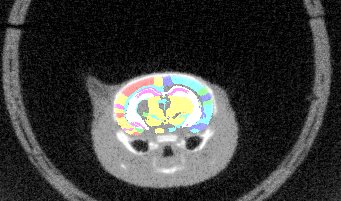

Slice2Volume (S2V) is a script/wrapper that registers Histology slices of arbitrary resolutions to volumetric image data with Elastix registration tool.

| Overlay of co-aligned CT scan and brain atlas-staining | Overlay of co-aligned CT scan and DAPI-staining | Overlay of co-aligned brain Atlas and DAPI-staining |

Reconstructing 3-dimensional volumes from single histological slices features the inevitable "banana problem". Aligning histological slices with a pre-defined volumetric image (CT, Atlas, etc) circumvents this problem. S2V uses the volumetric image as ground truth volume image (target image), the histological images are transformed into the volumetric coordinate system with a contour based approach.

- Downsampled and interpolated volumetric image of the transformed histological slices (see above)